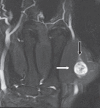

Results: The mean age of the eight patients was 40 (range 27-57) years. The most common presenting feature was a palpable mass. The mean interval between surgical treatment and the onset of clinical symptoms was 17.1 (range 4-72) months. Six of the eight tumours (75.0%) were located in the lower limb, while 2 (25.0%) were located in the upper limb. None of the patients had any preoperative neurological deficits. Tinel's sign was present in one patient. Magnetic resonance (MR) imaging showed that the findings of split-fat sign, low signal margin and fascicular sign were present in all patients. The entry and exit sign was observed in 4 (50.0%) patients, a hyperintense rim was observed in 7 (87.5%) patients and the target sign was observed in 5 (62.5%) patients. All patients underwent microsurgical excision of the tumour and none developed any postoperative neurological deficits.

Conclusion: Intramuscular schwannomas demonstrate the findings of split-fat sign, low signal margin and fascicular sign on MR imaging. These findings are useful for the radiological diagnosis of intramuscular schwannoma.